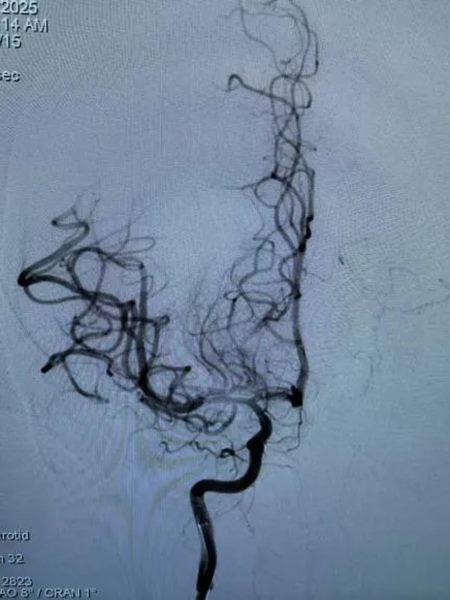

“医生,救救我的孩子!”清晨,郑大五附院急诊科的宁静被焦急的呼救打破。接诊医生发现,12岁的言言病情极为罕见且危重,初步判断为急性脑梗死。

▲ 入院时脑血管造影

时间就是大脑,时间就是生命。医院立即启动脑卒中绿色通道。神经内科一病区田小瑞医生火速抵达现场,经紧急评估,确诊“急性脑梗死”。然而,一个严峻的挑战摆在面前:言言未满18岁,不符合常规溶栓指征。生命通道,似乎被堵上了一道门。